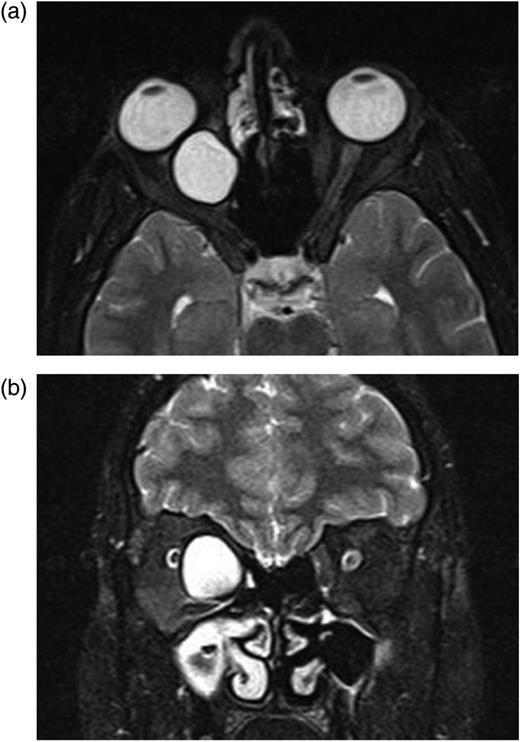

After second operation, in the first postoperative month, her ocular motilities were not restricted. Visual acuity was maintained at the same level (1/10). Control MR revealed no cystic structure except granulation tissue (Fig. 5a and b).

(a and b) After second operation, Control MRI in the first postoperative month shows granulation tissue.